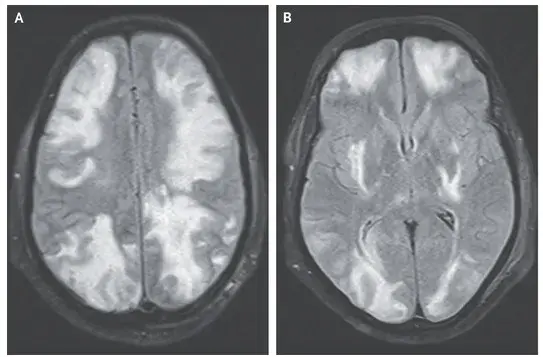

Neste vídeo, abordamos estratégias para lidar com pacientes com nefropatia membranosa que não respondem ao tratamento inicial. Ele enfatiza a importância da reavaliação constante e do ajuste do regime de tratamento com base nos resultados e no estado do paciente.